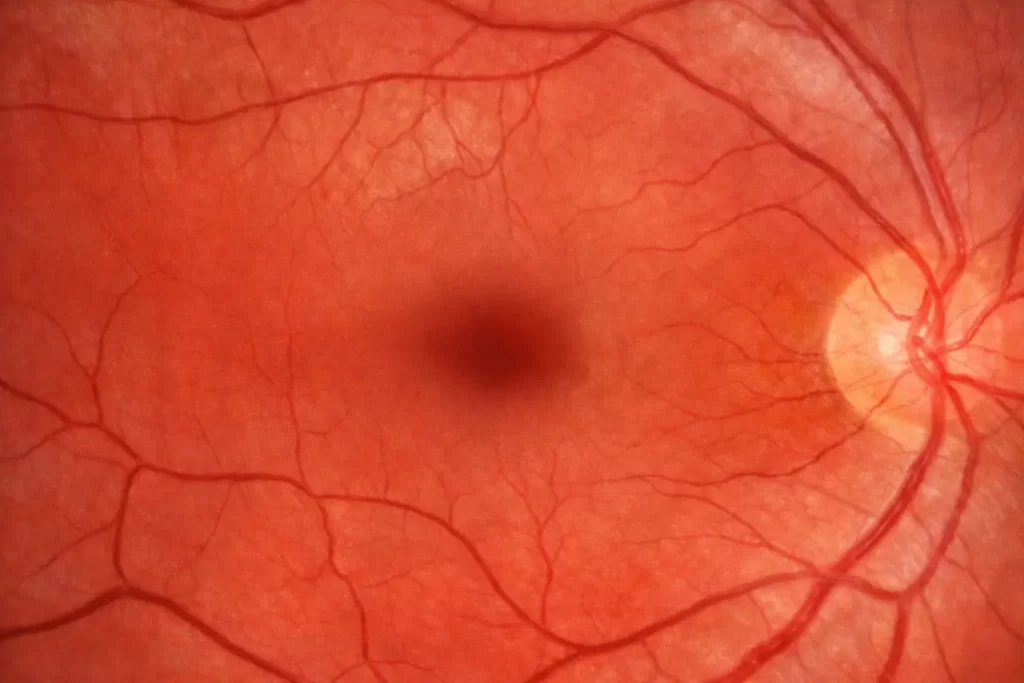

Na prática, sim. Você pode encontrar o exame com nomes diferentes, como fotografia do fundo do olho ou retinografia colorida. A ideia central é a mesma: usar uma câmera específica para registrar retina, vasos e disco óptico (região do nervo óptico) em imagem de alta qualidade.

A retinografia é uma foto: ela documenta a aparência do fundo do olho em 2D, ótima para comparar ao longo do tempo. Já o mapeamento de retina (muitas vezes feito com oftalmoscopia e lentes específicas) é um exame clínico detalhado, em que o médico observa a retina ao vivo, com diferentes aumentos e perspectivas, e pode ampliar bastante a avaliação periférica.

Quando falamos em prevenção de perda visual no diabetes, o objetivo é detectar alterações cedo. A retinografia aparece com frequência porque padroniza imagens e viabiliza comparações ao longo do tempo — inclusive em modelos de rastreamento, triagem e encaminhamento para especialistas quando necessário.